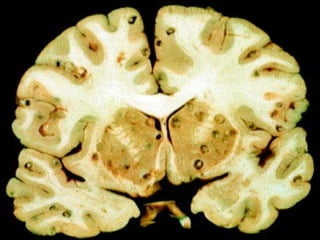

cisticercos

•C) Cestódios (em formade fita, com o tronco subdividido em anéis ou proglotes). Todas as tênias pertencem a este grupo.

Um exemplo comum éa Taenia solium, a "tênia do porco" e do homem, conhecida desde a Antigüidade

•Ela possui uma “cabeça” diminutaem forma de botão, o escólex, com quatro ventosas musculares nos lados e um circulo de ganchos na ponta elevada ou rostelo.

Um curto “pescoço”,colo ou zona de brotamento, liga o escólex ao tronco ou estróbilo, o qual consiste de uma série de até 1.000 proglótides. As ventosas e ganchos servem para fixar o escólex à parede intestinal do hospedeiro e a cadeia de proglótides permanece livre na cavidade intestinal.

Novas proglótides sãoconstantemente formadas por brotamento transversal no colo, estrobilização, permanecem unidas e são empurradas para trás pelo crescimento de outras mais jovens. A medida que se movem para trás, as proglótides aumentam de tamanho, amadurecem sexualmente e finalmente destacam-se.